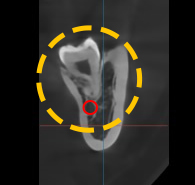

치근단 사진을 촬영하여

확인해보니,뿌리 끝까지

깔끔하게 잘 뽑혀나간 모습이

관찰되고 있네요!

하치조 신경과도 닿지 않고

무사히 뽑혀나가서 정말 다행입니다 🙂